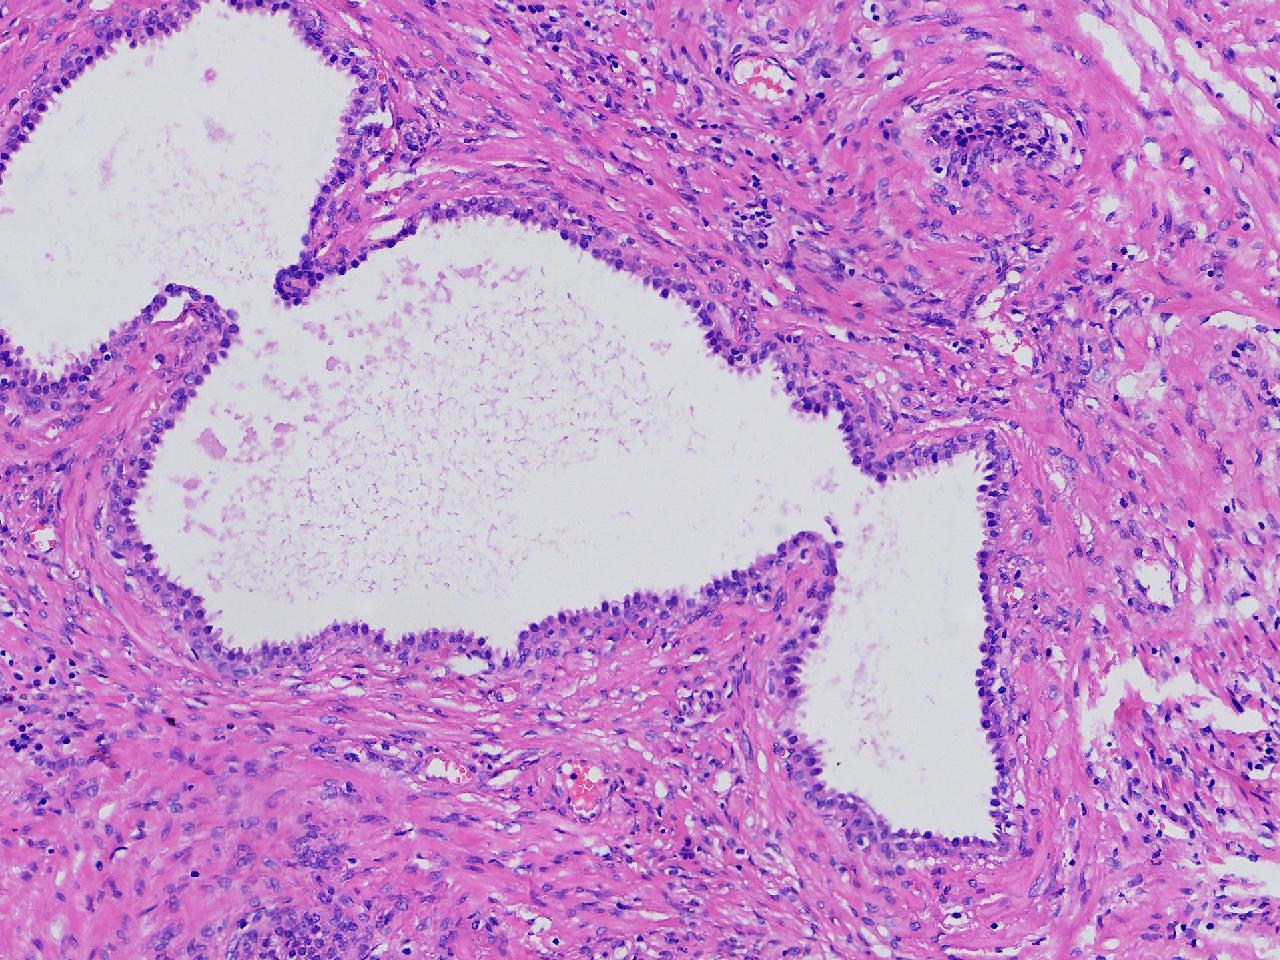

良性前列腺增生?

男,68岁,前列腺电切标本。

前列腺电切标本

灰粉色条索状软组织多块,5X4X3厘米。

前列腺增生。

BPH.